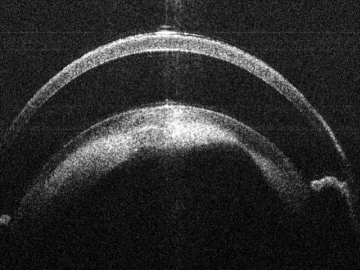

Anterior Segment

Bioptigen sdOCT Subretinal Image